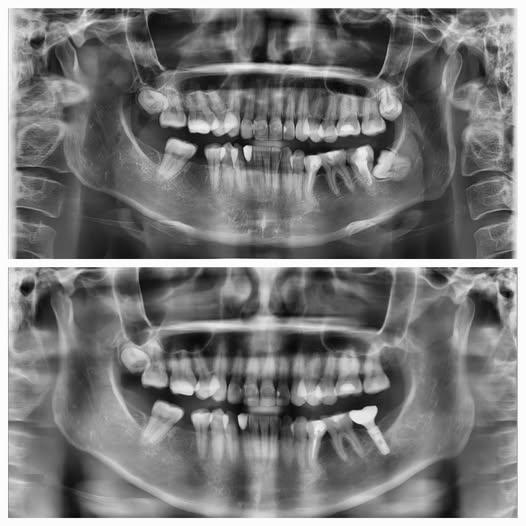

Khi răng khôn mọc lệch – “Thủ phạm” âm thầm làm mất răng bên cạnh

Không phải ai cũng biết rằng, răng khôn mọc sai hướng không chỉ gây đau nhức tạm thời mà còn có thể là nguyên nhân dẫn đến mất răng vĩnh viễn. Trường hợp bệnh nhân này là một minh chứng điển hình: phim X-quang cho thấy răng khôn hàm dưới bên trái mọc lệch ngang, đâm trực tiếp vào chân răng số 7 bên cạnh. Áp lực kéo dài âm thầm khiến răng khôn bị tiêu xương vùng xa, sâu nặng ở chân răng và cuối cùng không còn đủ điều kiện để giữ lại.

Trước mức độ tổn thương không thể hồi phục, ThS, BS CKII Dương Minh Tùng đã chỉ định nhổ bỏ cả hai răng, đồng thời tiến hành cấy Implant tại vị trí răng số 7 nhằm phục hồi chức năng nhai cho bệnh nhân. Giải pháp này không chỉ đảm bảo lực nhai bền vững như răng thật, mà còn giúp bảo tồn cấu trúc xương hàm, ngăn ngừa tiêu xương trong tương lai, điều mà cầu răng hay hàm tháo lắp không thể làm được. Đây là lý do vì sao Implant luôn là lựa chọn ưu tiên trong các trường hợp mất răng hàm quan trọng.

Cấy ghép Implant trong trường hợp mất 1 răng

Trường hợp bệnh nhân này bị mất răng cối nhỏ hàm dưới bên trái (răng số 35). Khoảng trống đã tồn tại trong thời gian dài, dẫn đến hiện tượng tiêu xương tại vùng mất răng, gây ảnh hưởng không nhỏ đến khả năng ăn nhai cũng như sự ổn định của toàn bộ hàm. Sau khi thăm khám lâm sàng và đánh giá kỹ qua phim X-quang toàn cảnh, đội ngũ bác sĩ tại Platinum xác định chất lượng xương vẫn đủ điều kiện để tiến hành cấy ghép mà không cần ghép xương bổ sung.

Chúng tôi lựa chọn trụ Implant có kích thước phù hợp, đảm bảo tích hợp chắc chắn với xương hàm. Nhờ ứng dụng công nghệ hiện đại, quy trình cấy ghép được thực hiện chính xác, an toàn và ít xâm lấn. Sau khi trụ ổn định, răng sứ được thiết kế bằng công nghệ CAD/CAM và gắn lên Implant, đảm bảo cả về thẩm mỹ, độ sát khít và khớp cắn lý tưởng. Không chỉ khôi phục chức năng nhai như răng thật, kết quả cuối cùng còn giúp bệnh nhân cảm thấy tự tin, thoải mái hơn trong sinh hoạt hằng ngày. Platinum Dental Group luôn đồng hành cùng khách hàng trong việc chăm sóc hậu phẫu, tái khám định kỳ và hướng dẫn duy trì kết quả lâu dài.